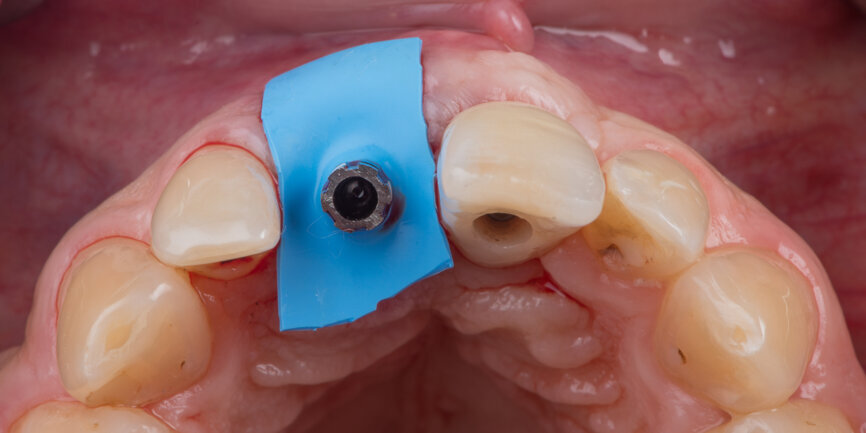

A Regular Base (RB) titanium temporary abutment for a crown was placed and a laboratory-made shell was positioned without interference with the temporary abutment (Fig. 9). The surgical site was protected with a small piece of rubber dam (Fig. 10), and the abutment was connected to the shell with a dual-curing luting composite (Fig. 11). The development of a proper emergence profile will be done extra-orally (Fig. 12) to produce the screw-retained temporary crown.